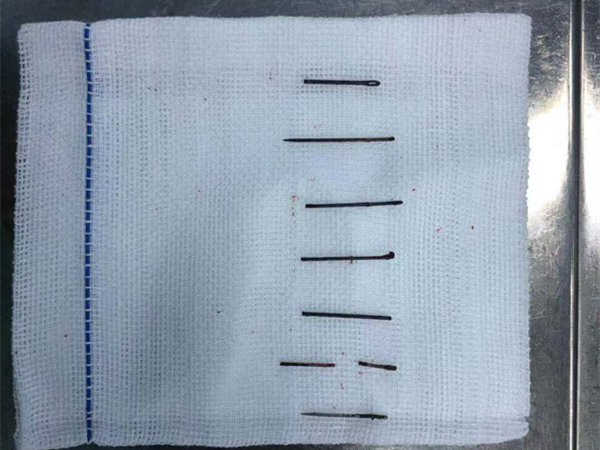

Allar átta voru fjarlægðar en myndin sýnir að þær voru orðnar dekkri og þykkari en þær voru upphaflega. Búist er við að Chen nái sér að fullu.